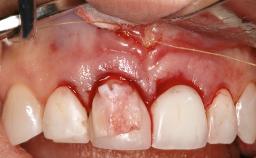

Resective Surgical Treatment of Peri-Implantitis Including Implantoplasty

In this case, Myroslav Solonko, Ignacio Sanz Sánchez and Mariano Sanz present a treatment that aims to eliminate exposed implant threads by modifying the implant surface, converting a moderately-rough surface into a smooth surface.